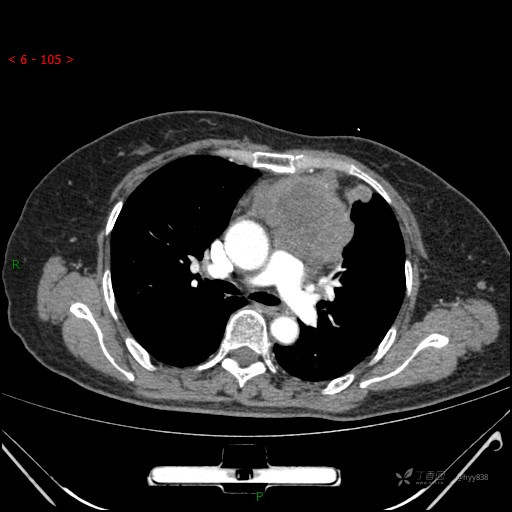

简要病史:患者诉3月余前患新冠肺炎,出现持续性胸闷,活动后可缓解,无胸前区压榨感,无畏寒发热不适,无胸痛咯血、呼吸困难,无恶心、呕吐,无腹痛、腹胀、腹泻等不适,未予以重视,未行特殊处理。患者胸闷持续存在,为进一步诊治,3天前于本院查胸部CT提示前纵膈团块状软组织密度影,肿瘤性病变可能,心包积液,左上肺磨玻璃结节,右下肺增殖灶可能建议进一步检查。门诊以“前纵膈占位” 收入我科。 患者本次起病来精神、食欲、睡眠尚可,大小便正常,体力、体重无明显变化。

辅助检查:CT

穿刺